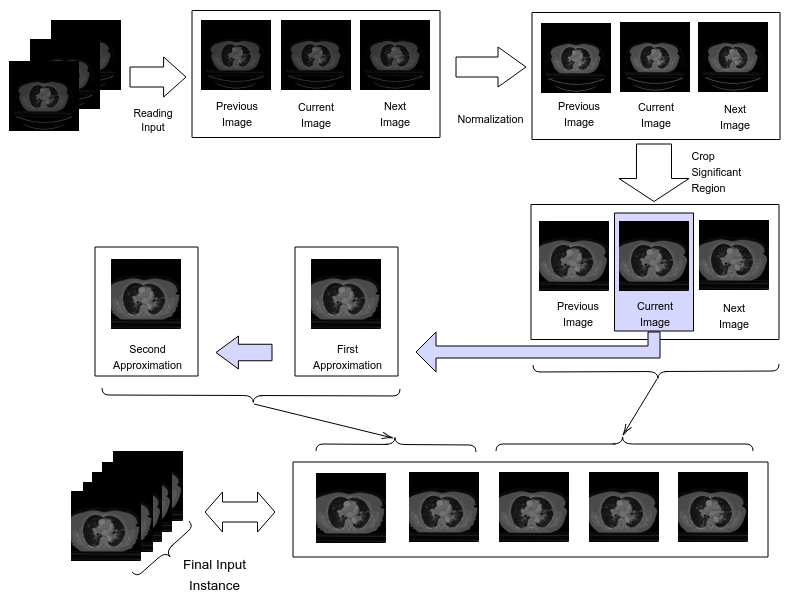

The final feature set comprised five slices concatenated one after another representing the original image, the previous and the next images, the first and the second approximations of the original image (by two-dimensional discrete wavelet transform). The training set was enlarged, or more accurately, doubled by augmenting the dataset, i.e., flipping or rotating each image based on a probability. Figure 1 illustrates the pre-processing steps to prepare the input instances.

A two-dimensional discrete wavelet transform was applied on each CT slice twice - generating first and second approximations of the image [28]. This operation simplifies images by leaving out some sharp horizontal, vertical and diagonal details. By analyzing the original as well as the transformed slices, the model can perceive tumor textures more minutely by identifying where these details were lost. In our study, the images were resized to .

The preprocessing step also involved gathering more information from neighboring CT slices. A tumor is a three dimensional structure and these CT images are only two dimensional slices of them. Principally, this calls for a three dimensional processing scheme which, however, is memory intensive. Nevertheless, whether a two dimensional slice would contain a tumor region or not would depend on its adjacent slices to a great extent. Therefore, to bring appropriate context and to account for dependencies between consecutive slices, the neighbors were added to each slice for preparing the input instance.

The masks generated had a lot of blank spaces surrounding the tumor region. This made the tumor fairly insignificant compared to the empty area. The images were, thus, cropped to a smaller window to ensure that an adequately amplified tumor portion is supplied to the model. We used the same co-ordinates to crop both the training and test sets, obtaining this window by analyzing the masks of the training set.

Based on the manufacturer, the DICOM files were initially partitioned into two groups. There was a stark difference in their span of intensity values in Hounsfield Unit (HU): from -1024 to 3071 for CMS Imaging Inc. and from 0 to 4095 for SIEMENS. Each partition was normalized to establish relative uniformity in the dataset.